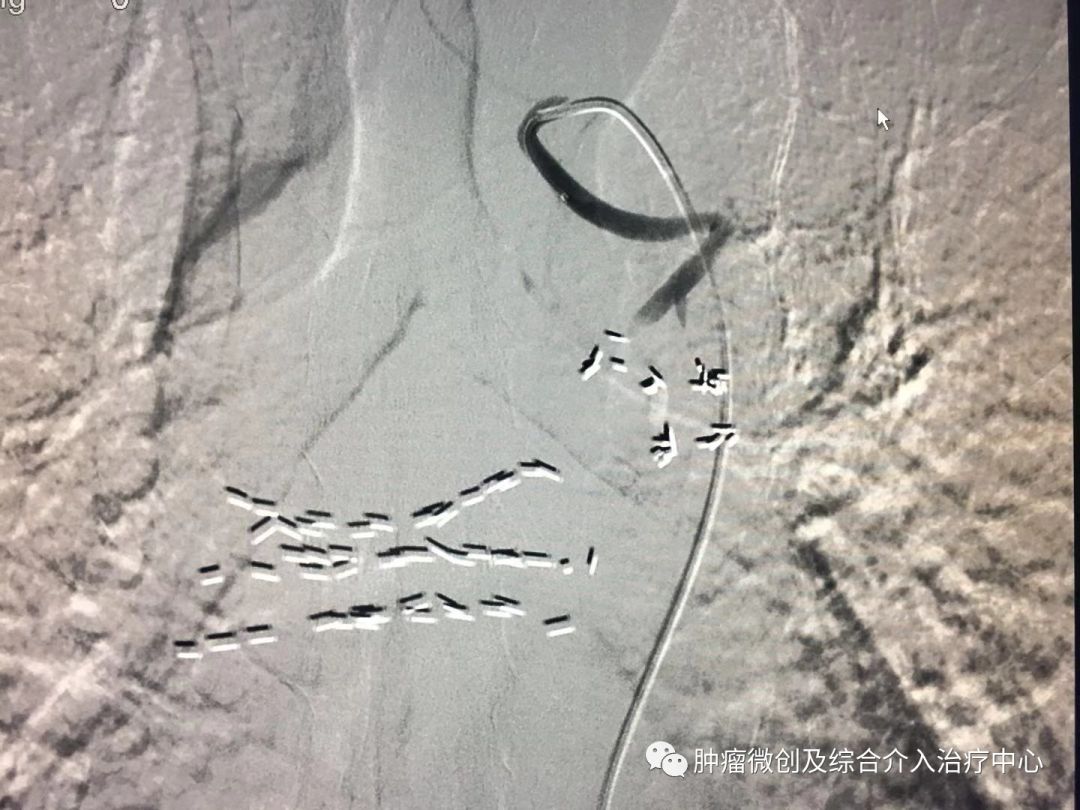

(肺动脉造影提示左肺动脉部分分支血管未显影,血栓形成,患者呼吸困难,胸闷、胸痛)

(经肺动脉导管溶栓治疗后,左肺动脉及其分支血管显影清晰,大部血栓溶解,患者呼吸困难症状改善,无胸闷及胸痛症状。)